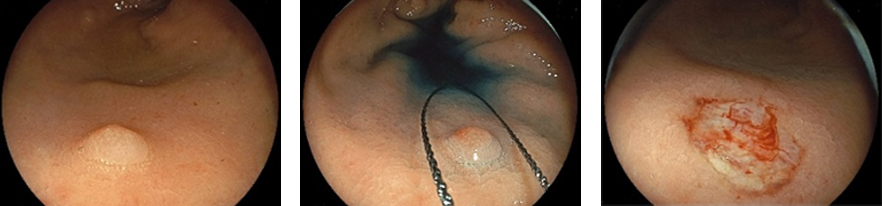

大腸ポリープを内視鏡により切除することは、大腸がんの発生率を低下させます。当院ではポリープの種類、サイズに応じて外来、入院でのポリープ切除術を施行しています。

大型生検鉗子で切除

スネアで切除

高周波通電による切除